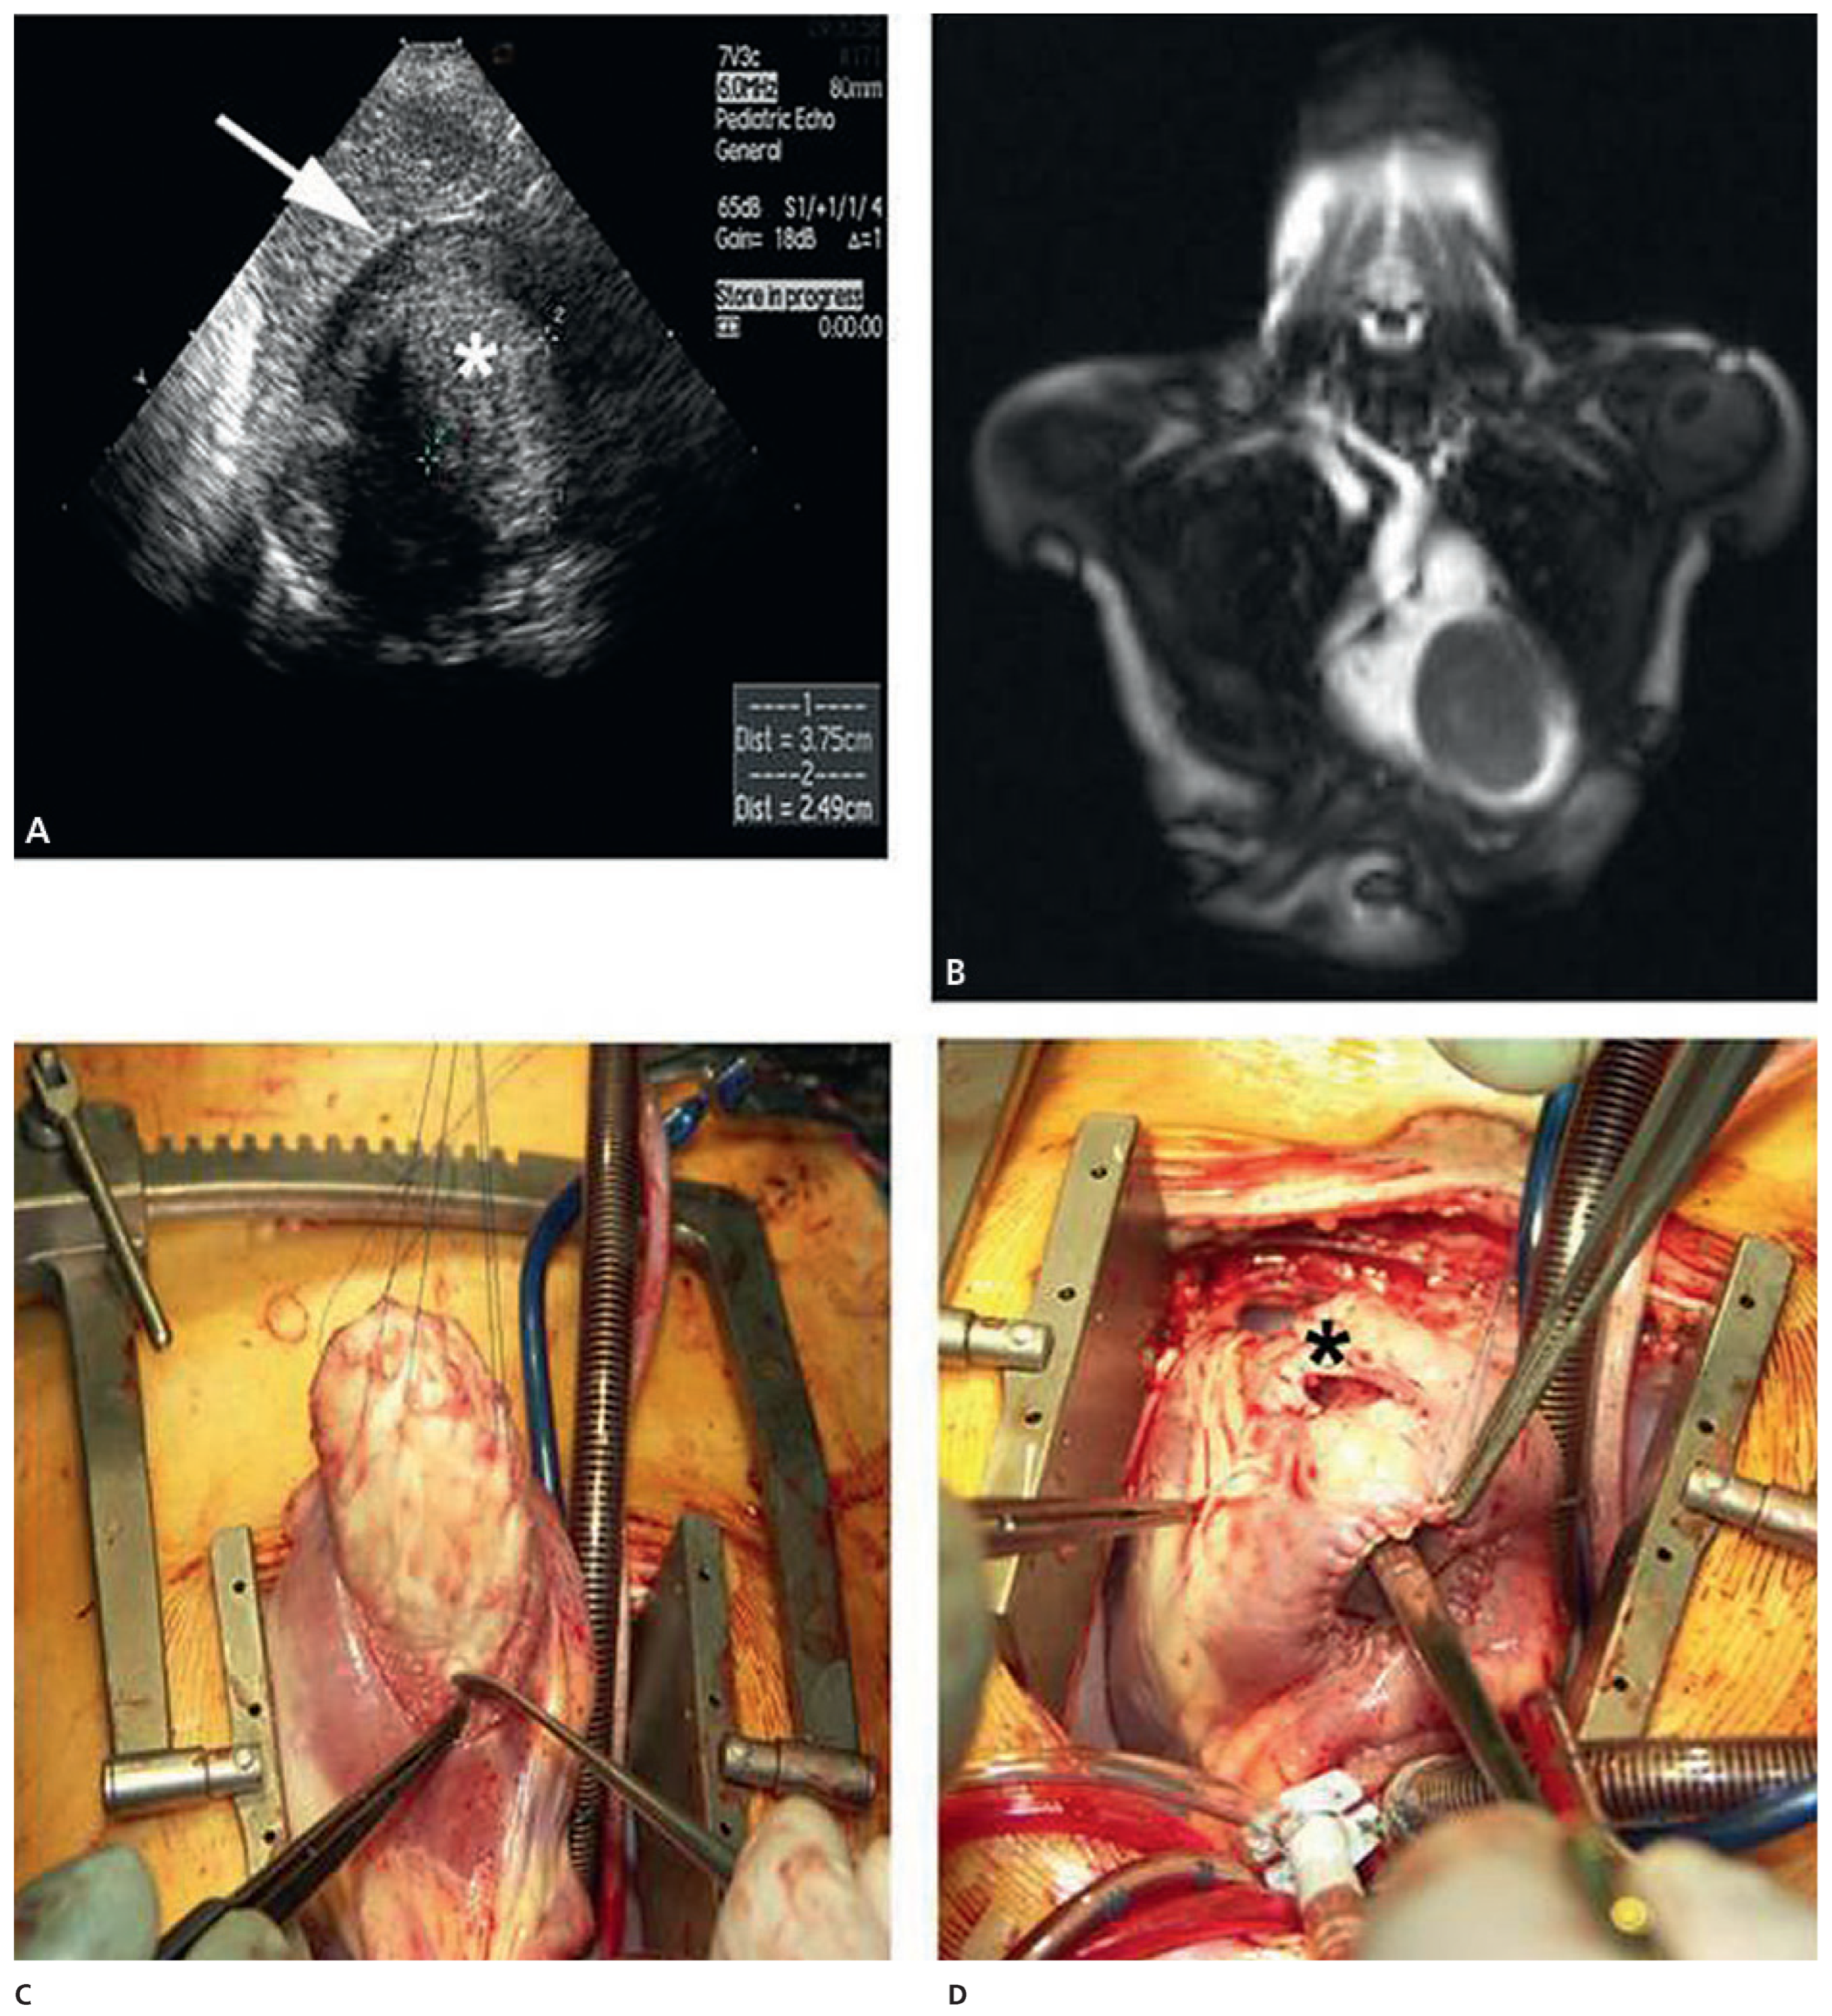

Case report 6: endometrial stromal sarcoma with extension into the right heart

- Renzulli, P.; Weimann, R.; Barras, J.P.; Carrel, T.; Candinas, D. Low-grade endometrial stromal sarcoma with inferior vena cava tumour thrombus and intracardiac extension: Radical resection may improve recurrence free survival. Surg Oncol. 2009, 18, 57–64. [Google Scholar] [CrossRef] [PubMed]